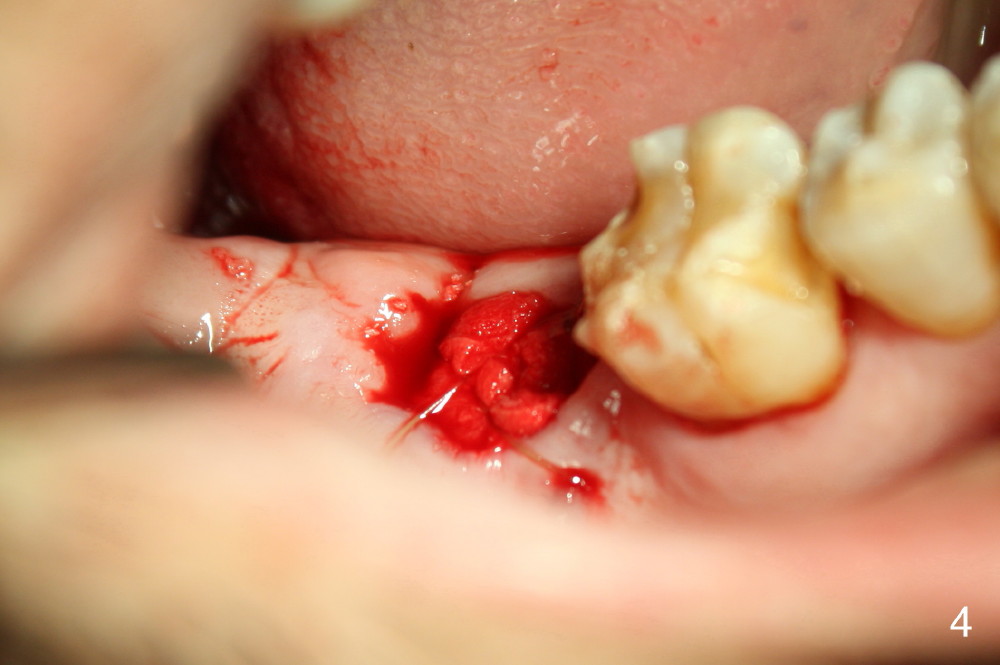

A 52-year-old man (heavy smoker) presents to office without schedule. He has severe pain at #31 and wants extraction immediately (Fig.1,2). He likes the idea of immediate implant, but we do not have time for it that day. Therefore the tooth is extracted (Fig.3). The socket is single. After debridement, bone graft (Fig.5 *) and collagen membrane (Fig.4) are placed.

To prevent nerve injury, a PA should be taken prior to implant placement, preferably using sensor 2. If bone density in the socket increases, a shorter implant can be used. Prepare implant positioners, which will be used to determine whether a tissue punch will remove too much keratinized gingiva or not. If the gingiva over the original socket is thin, #15 scalpel will be used to make a short mesiodistal straight incision (~10 mm for 6 mm diameter implant for example). Most importantly, try not to use drills. If there is need to use them, confine the drills within the original socket. It is possible to use taps to finish osteotomy (1, 2).